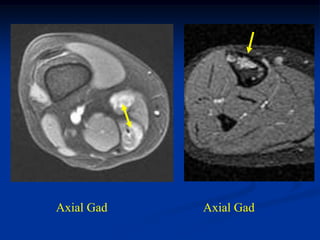

CLASSIC     Case #285         Sagittal T-1 MRI

67 year female with myxoid liposarcoma knee

Myxoid Liposarcoma The myxoid variant is the most common variant of the lipo- sarcoma and it is seen in a slightly younger age group between 40 and 50 years of age. It occurs in the lower extremities in 75% of cases, especially in the popliteal area. These lesions are slow growing and frequently asymptomatic in the early stages. On imaging studies, the MRI is the best method for visualizing these tumors that will have a mixed high and low signal on the T-1 weighted image because of the high percentage of fatty tissue in the tumor. Histologically, there will be evidence of malignant lipoblasts and it is common to find a plexiform network of small capillary tubes running thru the fatty tumor, similar to the capillary hemangioma. The prognosis for this variant is quite good after a wide local surgical resection, followed in most cases by local radiation therapy. The chance of pulmonary metastases runs as high as 20% and occasionally there will be multifocal myxoid

liposarcomas occurring inthe extremities as well as in retro- peritoneal locations. Occasionally, one will see a transitional form of myxoid converting into a higher grade round cell lipo- sarcoma which carries a more guarded prognosis.

CLASSIC Case #285 Sagittal T-1 MRI 67 year female with myxoid liposarcoma knee